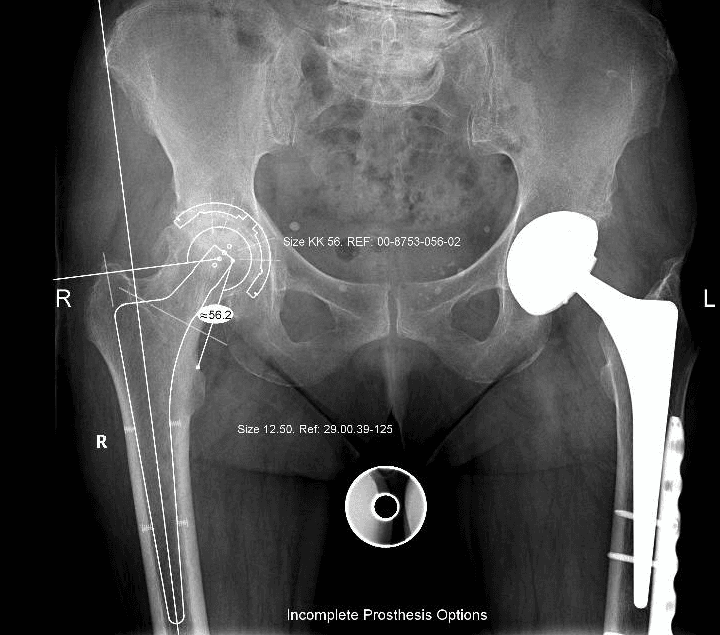

L’intervento di artroprotesi d’anca prevede la sostituzione dell’articolazione dell’anca mediante l’impianto di componenti protesiche in leghe metalliche, come il titanio, accoppiati a materiali plastici (polietilene di ultima generazione) e/o ceramiche. Questo processo include la sostituzione del femore prossimale (testa e collo) e il rivestimento della cavità acetabolare del bacino. L’obiettivo principale di questa procedura è ripristinare un’articolazione stabile e funzionale, migliorando significativamente la capacità di movimento del paziente, alleviando il dolore e migliorando la qualità della vita.

Esistono diverse vie d’accesso chirurgiche per l’artroplastica d’anca; quelle preferite nel nostro centro, a seconda delle caratteristiche del paziente, sono la via postero-laterale e la via anteriore. Ognuna di queste vie ha caratteristiche e vantaggi specifici, e la scelta è sempre basata sulle esigenze individuali del paziente.